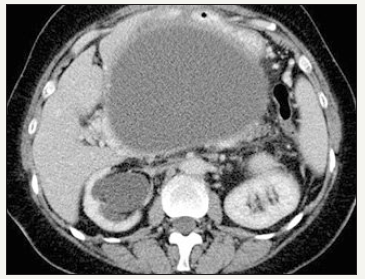

Figure 3A:Typical CT.

Figure 3B:Typical EUS appearance.

Figure 3: Pancreatic pseudocyst.

It is important to distinguish between such concepts as acute peripancreatic fluid collection, acute necrotic collection, walled-off necrosis, pseudocyst and abscess. The definitions of morphological features of acute pancreatitis are given in the Atlanta classification of acute pancreatitis -2012 [23]. Pseudocyst looks like monocystic lesion, usually oval or round-shaped, with a uniform, welldefined fibrous capsule without inner epithelial lining [23,24]. Communication with the pancreatic duct is absent (Figure 3A & 3B). The pancreas has signs of pancreatitis [25]. Pseudocyst contains of fluid that often transparent or brown, leaking, low viscosity, with high level of amylase and pancreatic enzymes. Sometimes, a small amount of debris can be detected in the lumen of the cyst [25]. In the case of infection of the cyst appear pussy contents. Pseudocyst located more outside the pancreatic parenchyma, in the zone of previous pancreatic necrosis, but in some cases the cyst may be partially or fully located in the parenchyma.